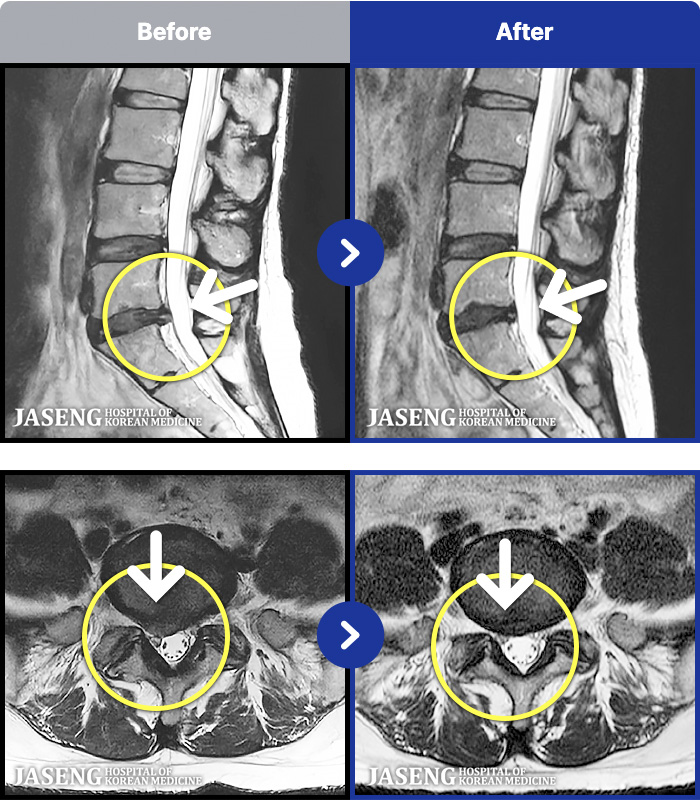

MRI ġ

1,299 MRI ũ ʸ Ȯϼ.